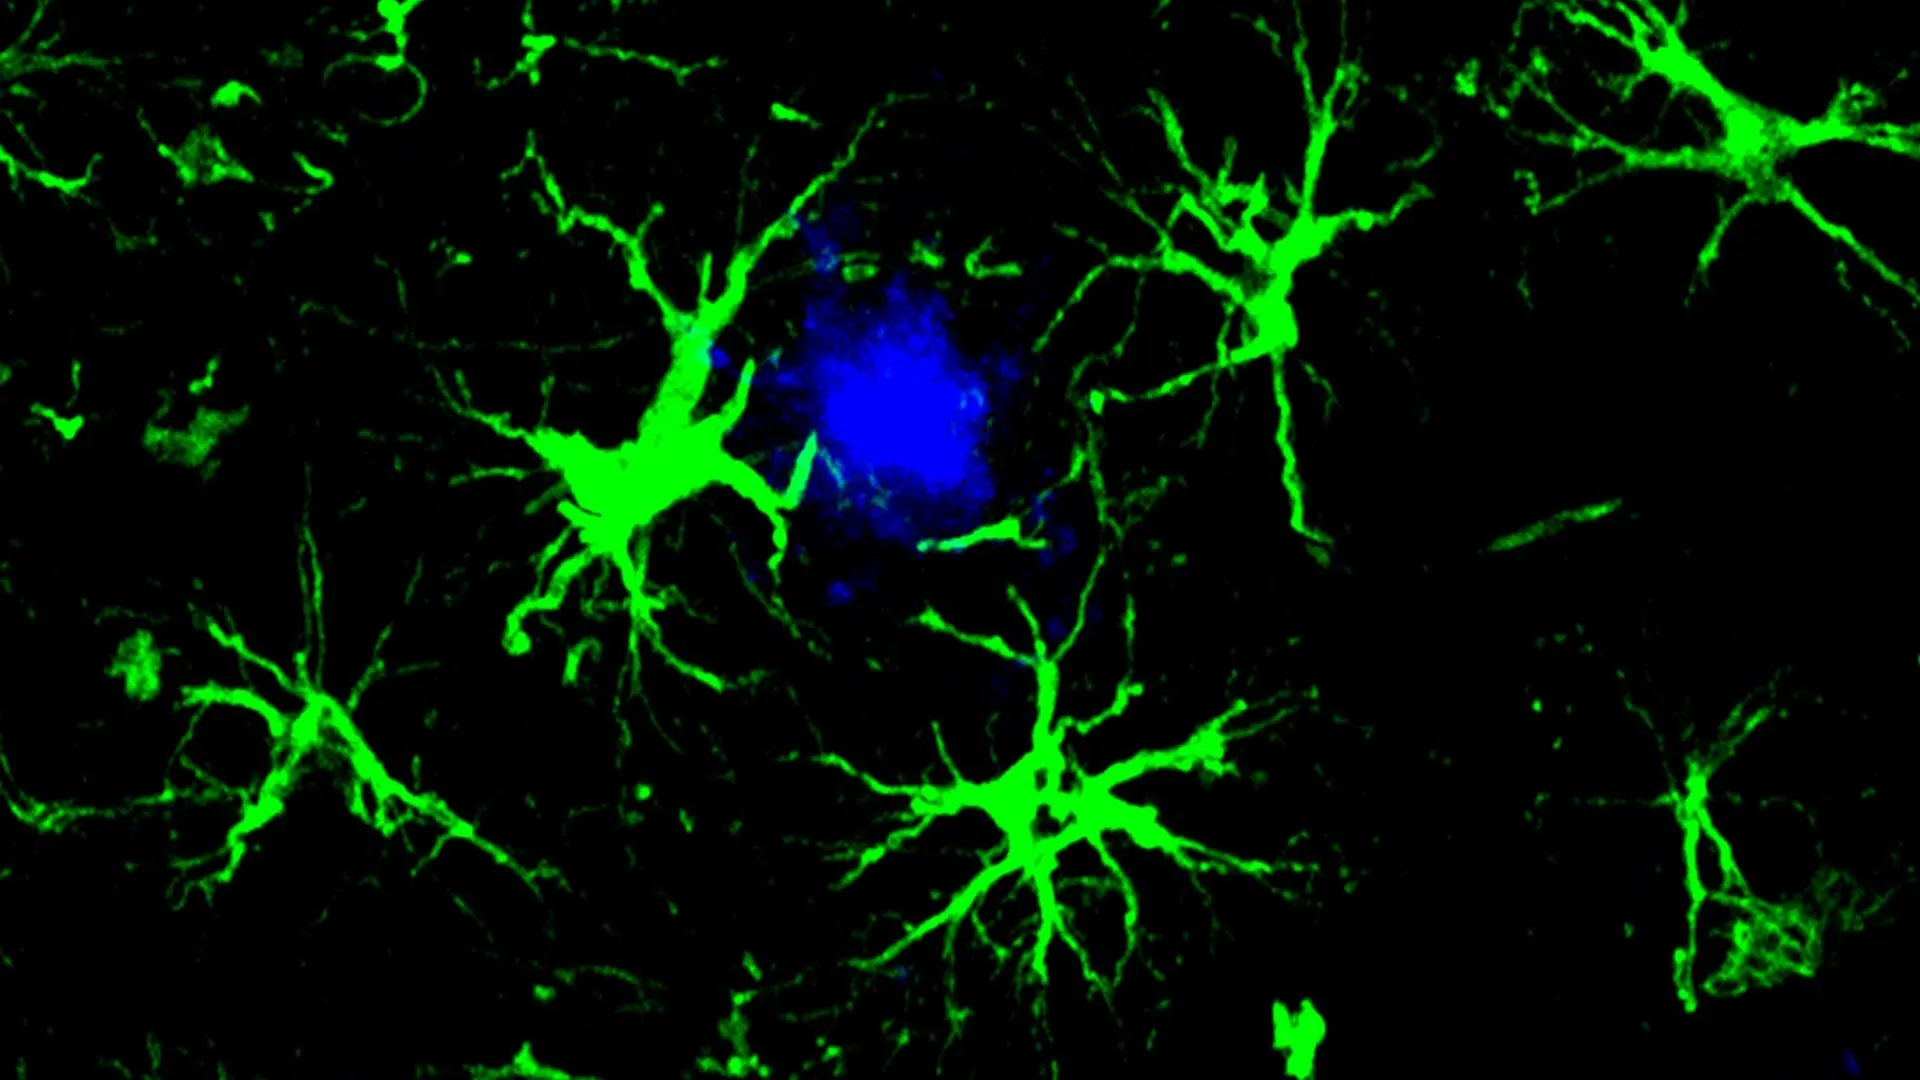

These genetically modified CAR-astrocytes function as highly specialized cellular agents within the brain’s intricate environment, performing a critical cleansing role. Their sophisticated design enables them to actively seek out and effectively dismantle the harmful protein aggregates, such as amyloid-beta, which are intrinsically linked to the progressive decline in cognitive function characteristic of Alzheimer’s disease.

The pathological cascade of Alzheimer’s disease commences with the aberrant accumulation of a sticky protein known as amyloid-beta, which coalesces into dense formations termed plaques. These deposits instigate a cascade of detrimental biological processes that ultimately lead to neuronal damage, brain atrophy, and a profound impairment of cognitive abilities. Under normal physiological conditions, the brain’s resident immune cells, microglia, play a vital role in clearing cellular debris and maintaining a healthy neural environment. However, in the context of neurodegenerative conditions like Alzheimer’s, these microglial cells can become overwhelmed by the pathological burden, compromising their capacity to effectively clear harmful substances from the brain.

To alleviate the strain on the compromised microglial system, the study’s lead author, Dr. Yun Chen, then a doctoral candidate working collaboratively in the laboratories of Dr. Colonna and Dr. David M. Holtzman, the Barbara Burton and Reuben M. Morriss III Distinguished Professor of Neurology at WashU Medicine, turned his attention to astrocytes. As the most abundant cell type in the brain, astrocytes are essential for maintaining neuronal health and providing crucial support functions. Dr. Chen undertook the task of reconfiguring astrocytes to function as specialized amyloid-clearing entities. This was achieved by introducing a gene encoding a chimeric antigen receptor (CAR) into astrocytes via the administration of a harmless viral vector. Once expressed on the astrocyte surface, the CAR molecule grants these cells the capacity to bind to and internalize amyloid-beta proteins. This augmented functionality directed the engineered astrocytes to specifically target and remove amyloid-beta plaques in mice genetically predisposed to developing these pathological hallmarks of Alzheimer’s disease, complementing their natural role in maintaining brain homeostasis.